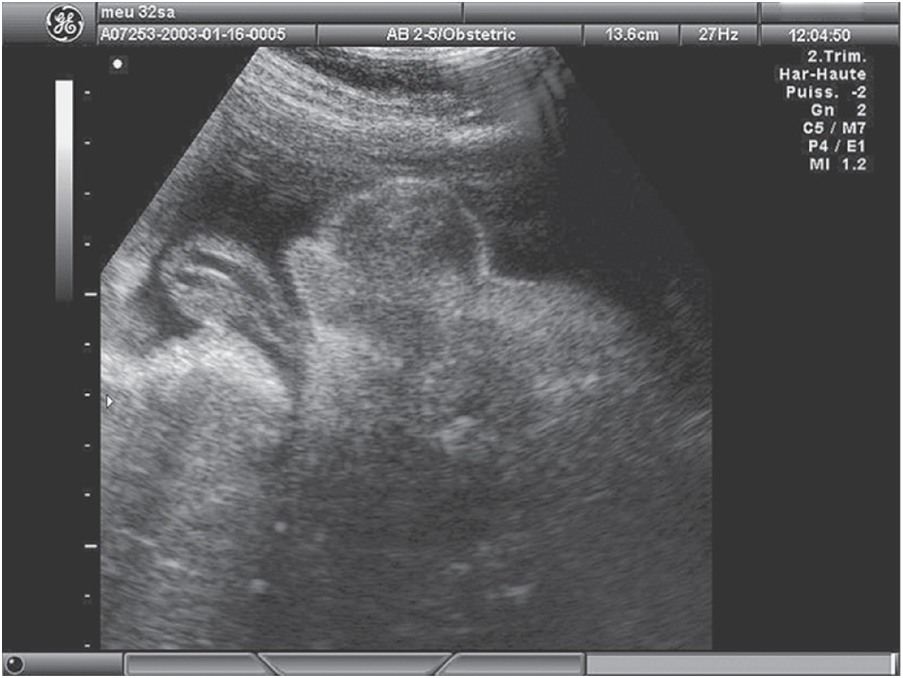

Dating scan (12-week scan , booking scan or due date scan ) At 12 weeks you will be able to see more detail and make out hands and feet . With a few exceptions from 10 weeks of pregnancy, you would normally have an abdominal ultrasound .

Early, dating and viability scans (6 - 15 weeks) Why have an early pregnancy scan ? . . . How is the scan carried out? Under 10 weeks the best way to see your baby and get clearer images is by carrying out a transvaginal scan (internal scan ) . However, if you would prefer to come with a full bladder we can start by scanning you this way and the . . .